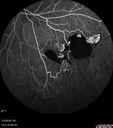

51 year old male with a broken vein in the left eye. His vision is pretty good. He has not noticed any vision change. You asked him to come here for further evaluation in the left eye. VA OD: sc20/63 PH20/25-2 NccJ1 VA OS: sc20/20 Patient had scatter laser to non-perfused retina and never had a vitreous hemorrhage (yet)

Coats' Disease -51 year old asymptomatic male450 views20/20 vision - had laser to non-perfusion because of proliferation.00000